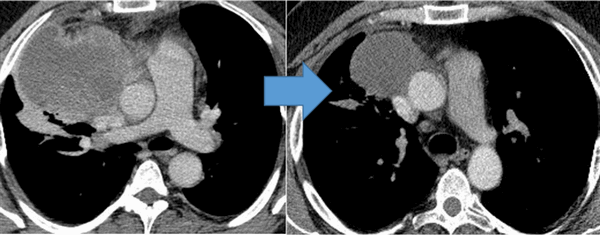

Показания к химиотерапии определяются степенью распространенности процесса, наличием легочных/внелегочных метастазов. Стандартным режимом химиотерапии при герминогенных опухолях является режим «BEP», включающий блеомицин, этопозид и цисплатин. Для пациентов с дыхательной недостаточностью, обширным поражением легких, во избежание легочной блеомициновой токсичности, как альтернативный вариант, может быть использованы режимы химиотерапии VIP (этопозид, ифосфамид, цисплатин) или ЕР (этопозид, цисплатин).

Для оценки эффективности химиотерапии каждые 2 цикла и после ее окончания проводится компьютерная томография исходных зон поражения, перед каждым циклом мониторинг уровня опухолевых маркеров. Рост маркеров на фоне лечения или после его завершения, а также замедление их снижения свидетельствует об активности опухолевого процесса и необходимости проведения второй линии химиотерапии.

![Герминогенная опухоль средостения до лечения и после 4х циклов химиотерапии по схеме «ВЕР » - уменьшение опухоли более чем на 50% (КТ грудной клетки).]()

Герминогенная опухоль средостения до лечения и после 4х циклов химиотерапии по схеме «ВЕР » — уменьшение опухоли более чем на 50% (КТ грудной клетки)